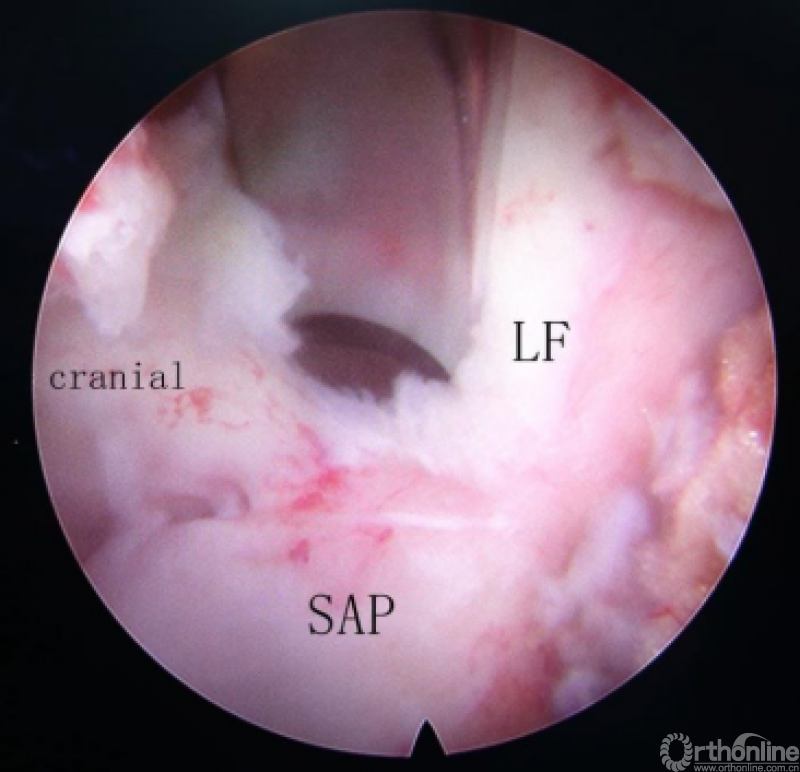

第四步“分”:分离上关节突及黄韧带;

第五步“咬”:咬除部分上关节突,显露椎间盘及神经根;